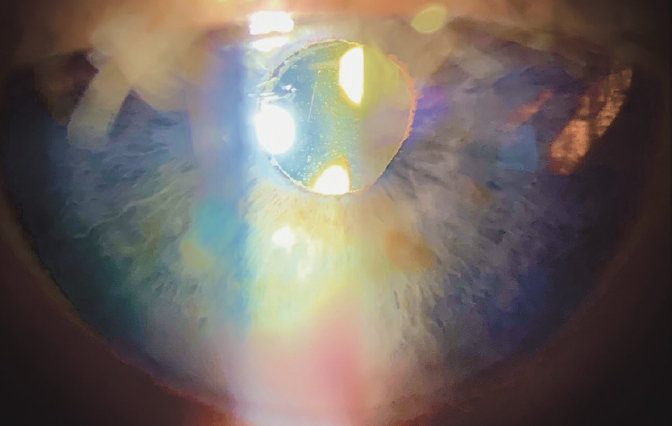

Fig. 3. Iris transillumination in haptic-iridal contact zone, microhyphema

Рис. 3. Трансиллюминация радужки в зоне её контакта с гаптическим элементом интраокулярной линзы, микрогифема

At examination, in the overwhelming majority of patients hyphema was revealed (93%), in 2/3 — ocular hypertension (66%), in a half (52%), there was a vitreous hemorrhage. Uveitis was revealed in 57% of cases. Unfortunately, in none of the case histories iris transillumination was mentioned, in spite of the fact that this sign is encountered in the UGH syndrome extremely frequently — up to 90% [10] (Figure 3).

Thus, the UGH syndrome by no means obligatory suggests the presence of a classic triad “uveitis–glaucoma–hyphema”. The most significant diagnostic sign of this disease appeared to be the presence of blood in the anterior chamber fluid. No less important criterion is the iris transillumination. It could also be a sign of herpetic uveitis, but develops by this condition significantly more rarely than in the UGH syndrome (40 and 90%, correspondingly) [10]. Moreover, the combination of iris transillumination and hyphema in a pseudophakic eye makes the differential diagnosis of these two conditions substantially more easy.